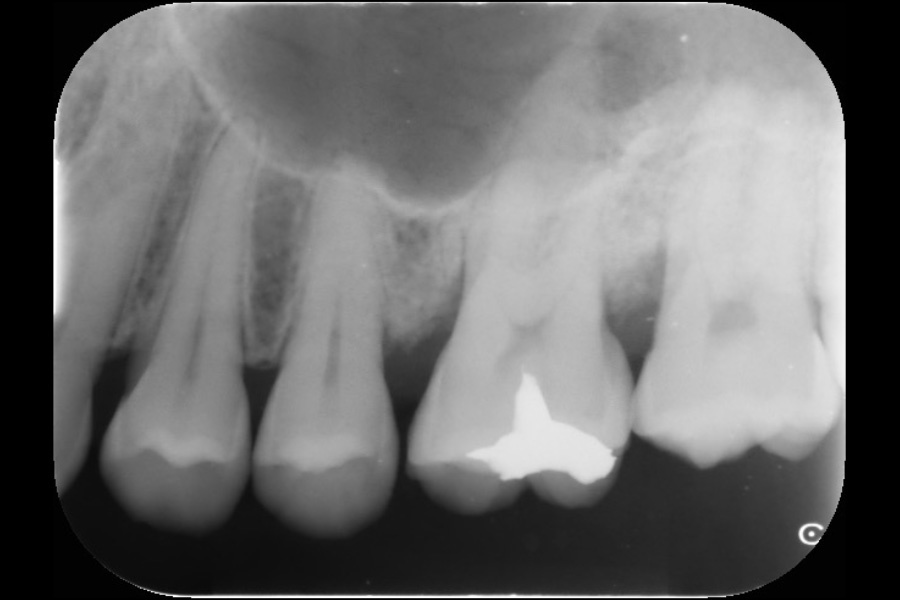

上の前歯の歯ぐきが腫れた

【歯周組織再生療法】

- 主訴

- 上の前歯の歯ぐきが腫れた

- 治療内容

- 左上3近心に垂直性骨吸収が認められたためエムドゲインと骨補填材を用いて歯周組織再生療法を行った

- 治療に伴うリスク

- 歯肉退縮、知覚過敏